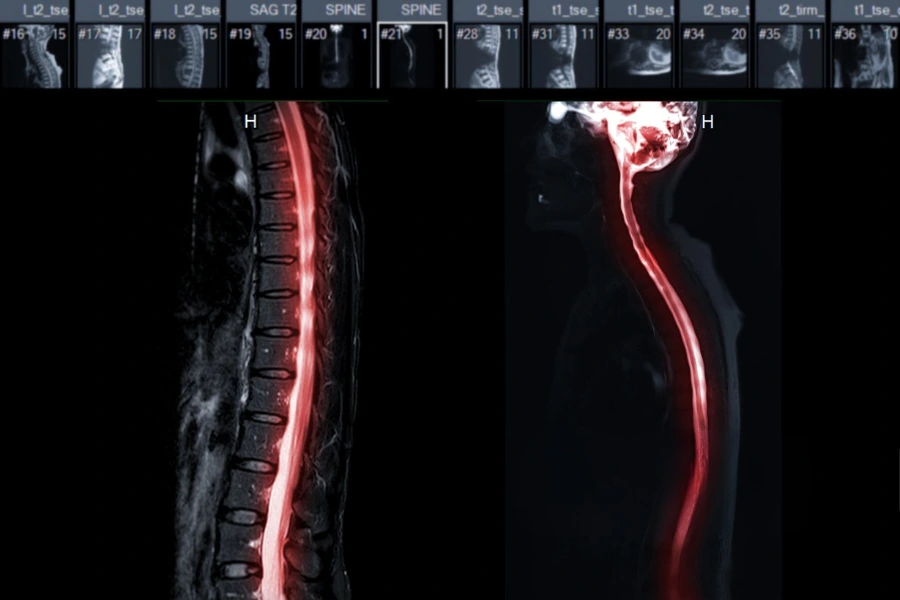

Діагностика стенозу хребетного каналу починається з ретельного клінічного огляду, який дозволяє оцінити неврологічні функції, зокрема силу м’язів, рефлекси, чутливість шкіри та характер рухових порушень. Проте вирішальну роль у підтвердженні діагнозу відіграють інструментальні методи, серед яких МРТ хребта є ключовим та найбільш інформативним.

Магнітно-резонансна томографія дає можливість отримати високодеталізовані зображення м’яких тканин, міжхребцевих дисків, зв’язок і нервових структур, які формують хребетний канал. За допомогою МРТ лікар може точно визначити ступінь звуження, побачити компресію спинного мозку або нервових корінців, відрізнити відносний стеноз від абсолютного і виявити супутні патології, такі як протрузії та грижі дисків, кісти, гіпертрофія зв’язок чи артроз. МРТ також дозволяє оцінити набряк, запалення та зміни в нервовій тканині, що неможливо побачити на інших видах обстежень.

У складних випадках також може призначатися комп’ютерна томографія, яка краще візуалізує кісткові структури й допомагає уточнити анатомію хребців. Іноді додатково проводять електронейроміографію для оцінки функції нервів, якщо симптоми не повністю корелюють з даними візуалізації. Такий комплексний підхід до діагностики дає можливість повністю зрозуміти причину стенозу, оцінити ступінь ураження та обрати оптимальну тактику лікування, орієнтуючись на індивідуальні особливості пацієнта.